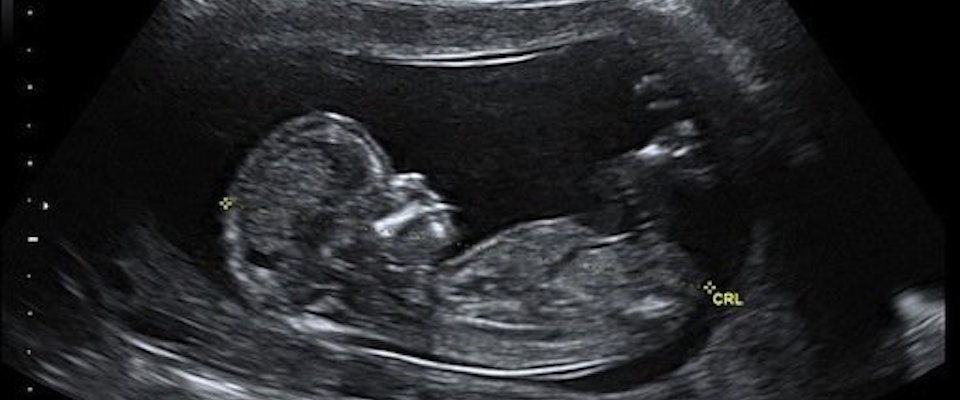

Every young expectant couple I know today, without exception, when they have a prenatal visit, hope they will get to see the baby. Every baby’s photo book today has a sonogram for its first picture. The first pictures, and there are often many of them, are prenatal.

And it is changing how parents talk about their child. “Our little guy,” one couple recently told me, “he’s as big as my thumb.” Or: “Our baby would now fit in the palm of my hand.” They delight in seeing the baby’s limb, the head, the sex, even fingers. They delight in seeing the heart and looking into its chambers.

What is happening, largely unnoticed and far below the radar of the political debates, is that our culture’s visual imagination of the human is expansively changing. We used to picture the human life cycle as going from birth to death. But adults who are now becoming parents, along with their friends and an increasingly wider circle, no longer think it strange to consider and picture as a human being, as one of us, one whose weight is measured in ounces rather than pounds and whose size is given in terms of a portion of one’s own hand.

The change is this: Thanks to technology’s advance, it is increasingly not weird to visualize and speak of humans by name who never weighed more than a pound. Or half a pound. Or less.

I did not speak or even much think of my stillborn sister, even though she was pretty much full term. But today we can see with our eyes and thus have the boldness to speak with our lips what we previously knew but couldn’t visualize: that some of our brothers and sisters would easily have fit in the palm of even a very small hand.